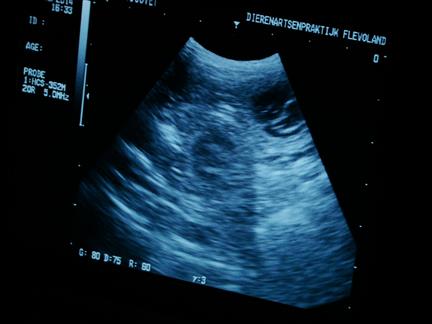

| maar in de donkere ronde vlekken |

zie je witte lijntjes |

| en dat zijn .......... de puppies :-) |

ook zijn de hartjes al aan het kloppen, allemaal prachtig om te zien |